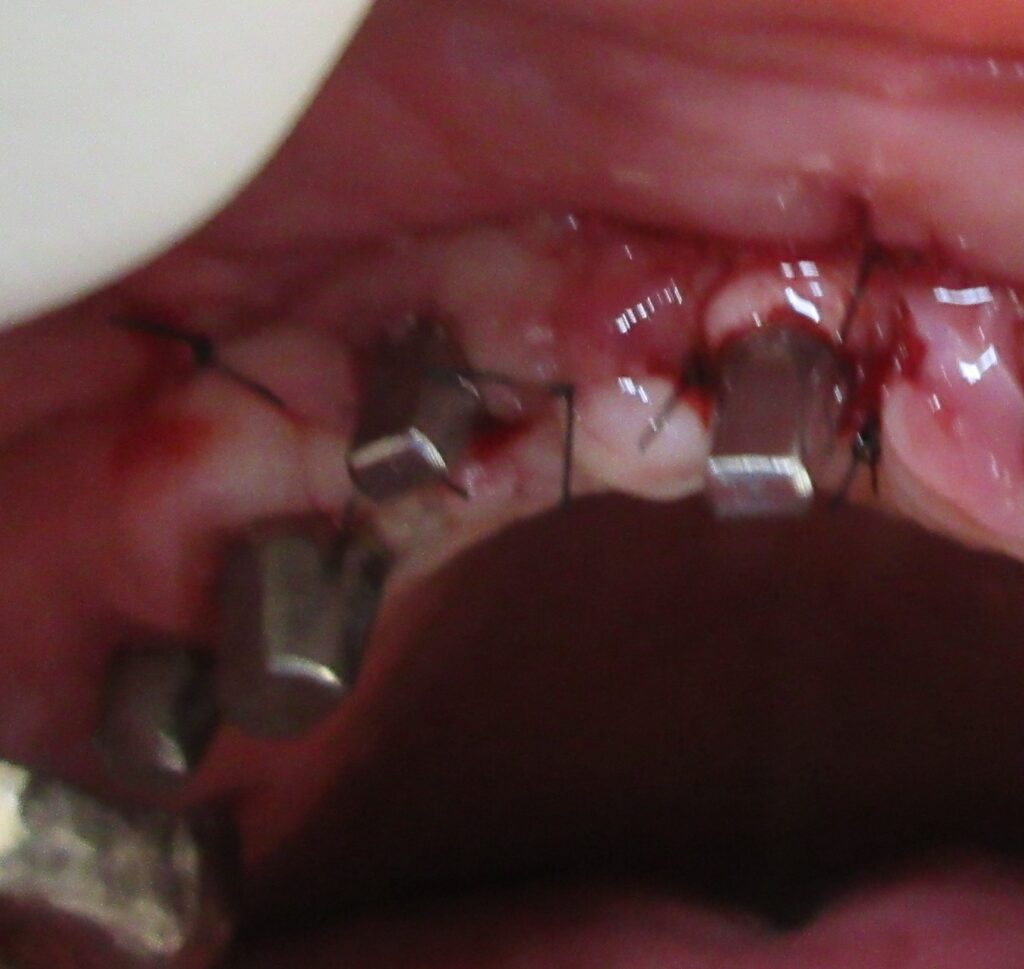

麻酔が効いている事が確認されると、すぐにオペ開始です。

まずは右上1番目の歯茎から骨の部分までを穴開けパンチの要領で穴を開けていきます。

くりぬいた部分の歯肉を取り除き、次は骨に穴を開けていきます。

ドリルの先端を細い物から徐々に大きい物に変えながら、植立するインプラント体のネジの部分を除いた胴の部分の太さに合わせた大きさの穴を開けていきます。

開けた穴に、専用道具を使ってネジを締めるように長さ2センチ程のインプラントを骨に埋め込んでいきます。

続けて他の歯も同じように植立していきます。

インプラントオペでは、複数本を植立する場合でも、当時進行はせず、1本ずつ同じ工程を繰り返して植立します。

しっかりとインプラント埋め込まれた後は、動揺がないか、噛んだ時に当たらないかなどを確認して、最後にパノラマ写真を撮影して今回のオペは終了となりました。